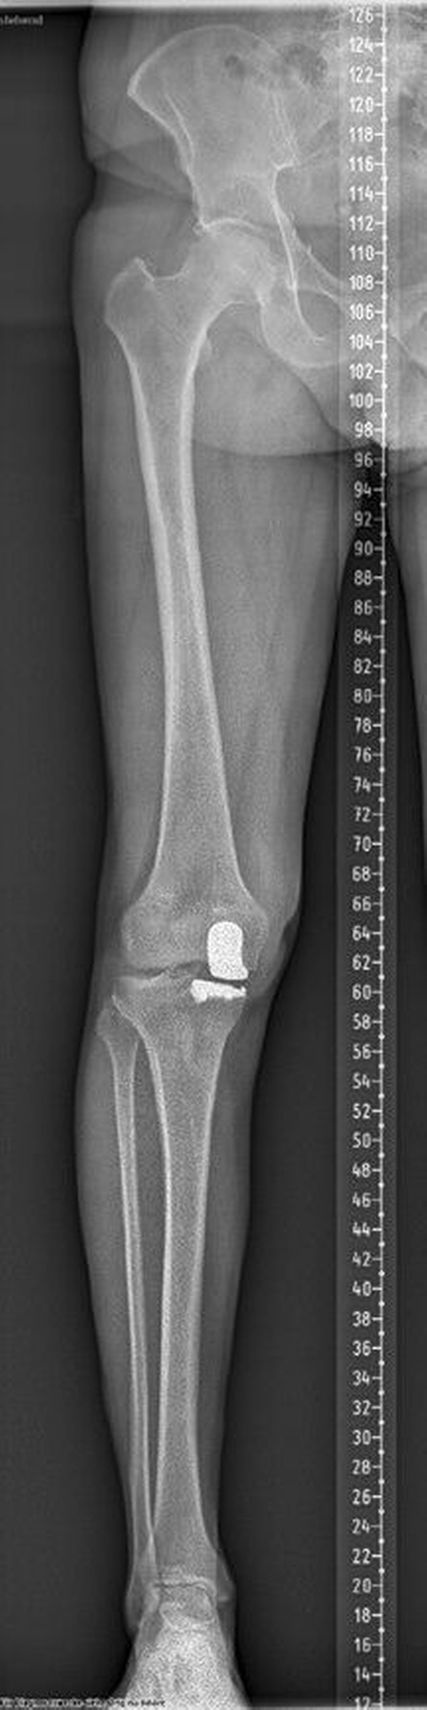

Relevanz der Beinachse bei der Therapie von degenerativen Meniskusläsionen